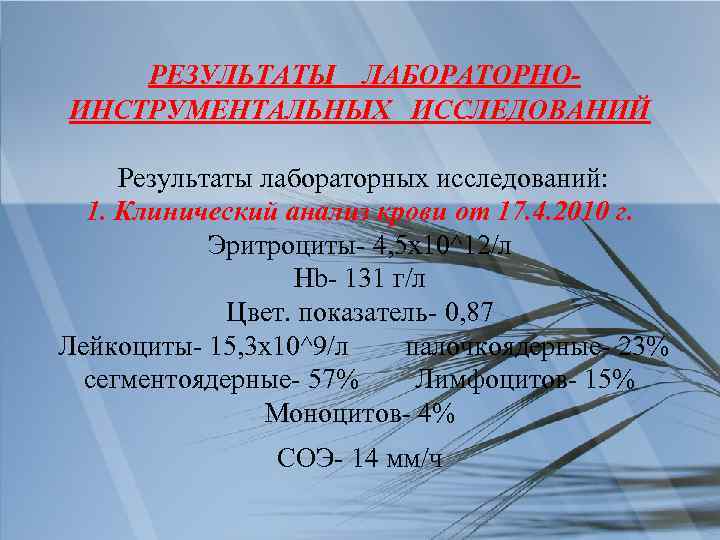

РЕЗУЛЬТАТЫ ЛАБОРАТОРНОИНСТРУМЕНТАЛЬНЫХ ИССЛЕДОВАНИЙ Результаты лабораторных исследований: 1. Клинический анализ крови от 17. 4. 2010 г. Эритроциты- 4, 5 х10^12/л Hb- 131 г/л Цвет. показатель- 0, 87 Лейкоциты- 15, 3 х10^9/л палочкоядерные- 23% сегментоядерные- 57% Лимфоцитов- 15% Моноцитов- 4% CОЭ- 14 мм/ч